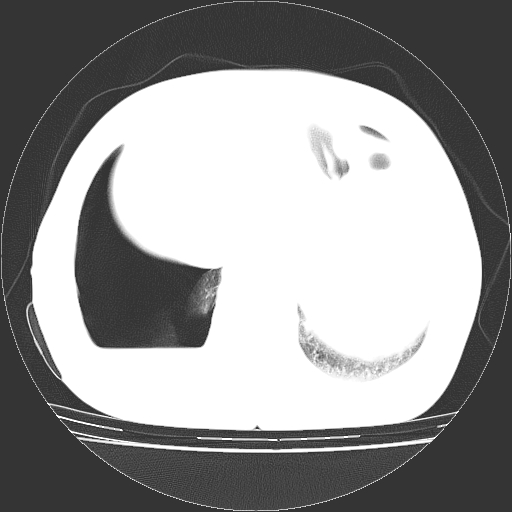

以下是引用zhangzhongshou在2008-3-22 12:52:00的发言:[br]1、右侧液气胸。[br]2、腹水。建议进一步检查。

以下是引用鲁巨ct在2008-3-22 14:10:00的发言:[br]1、右侧液气胸,右中下叶节段性不张。[br]2、腹水,建议上腹部ct检查

以下是引用zjzjr在2008-3-22 17:19:00的发言:[br]1、右侧液气胸,右下叶节段性不张。[br]2、腹水,建议上腹部ct检查